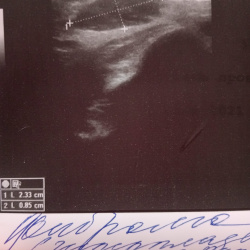

Образование молочной железы размерами около 11 мм в диаметре, не дающее акустической тени.Выполнена тонкоигольная аспирационная биопсия под УЗИ-контролем. Цитология рака молочной железы. Секторальная...